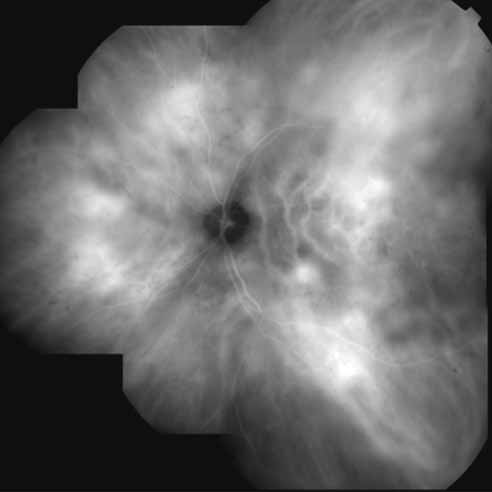

With this clinical diagnostic and histopathologic information available, pilot studies were performed to determine the practicality of using ICG angiographic guidance in the treatment of occult CNV. Slakter and associates28 performed laser photocoagulation treatment on 79 eyes with occult CNV. The occult CNV was successfully eliminated in 57% of patients who underwent ICG-guided treatment (Figs. 5 and 6). The authors found the success rate to be higher (66%) for patients with CNV not associated with PEDs than for those with PEDs (43%). Visual acuity improvement or stabilization was achieved in 57% of all patients. Recurrences were more frequent and more difficult to control in those patients who had associated PEDs on initial clinical presentation. Additional independent studies have reported similar diagnostic and treatment outcomes with the use of ICG angiography in patients with occult CNV.29,30